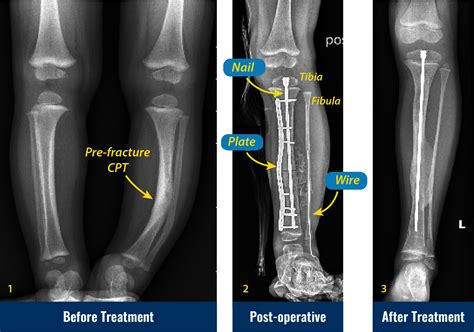

Alright, let’s get to the main event: the pseudoarthrosis tibia X-ray. This is the go-to imaging tool for docs trying to figure out if you’ve got this non-union thing going on. When they suspect pseudoarthrosis, the standard X-ray is usually the first step, and often, it’s enough to give them a pretty good idea. What are they actually looking for on these films, you ask? They’re hunting for signs that the bone hasn’t knitted back together . A healthy fracture healing will show progressive callus formation – that’s new bone trying to bridge the gap. In pseudoarthrosis, you’ll often see a clear gap between the broken bone ends, and instead of solid bone bridging it, there might be fibrous tissue or even cystic changes in the bone ends. Sometimes, the bone ends can become rounded off and sclerotic (that means hardened and denser) because they’re not being used properly, and the body’s trying to adapt to the instability. Another key indicator is motion at the fracture site . While you can’t directly see motion on a static X-ray, the consequences of that motion are visible. You might see widening of the fracture line over time, or displacement of the bone fragments that wouldn’t happen if the bone were solidly healed. They’ll also look at any hardware – like screws, plates, or rods – that might have been put in during initial surgery. Is the hardware intact? Is it loose? Is there any sign of infection around it (like bone resorption or bone spurs)? The X-ray is basically a detective’s magnifying glass, revealing clues about the past injury and the body’s current, failed attempt at repair. It’s essential to compare current X-rays with previous ones if available, as this allows the radiologist and orthopedic surgeon to track the progression (or lack thereof) of healing over time. This comparison is vital in confirming a diagnosis of pseudoarthrosis, as a single X-ray might not always be definitive, especially in the early stages of non-union.

Radiologists are like the skilled detectives of the medical world when it comes to interpreting X-rays. For a pseudoarthrosis tibia X-ray , they’re scrutinizing the image with a fine-tooth comb. The primary goal is to identify lack of bony union . This means they’re looking for a distinct gap between the fractured bone ends. In a successfully healing fracture, this gap would be filled with callus, a new bone formation that gradually ossifies. In pseudoarthrosis, this callus is either absent, inadequate, or has failed to mature into solid bone. They will specifically look for atrophic changes , which means the bone ends are thin, pointed, or have lost their normal shape due to disuse and lack of stability. Conversely, they might see hypertrophic changes , where the bone attempts to heal by forming excessive, often disorganized, bone spurs (callus) around the ends, but these spurs don’t actually bridge the gap. This is often called